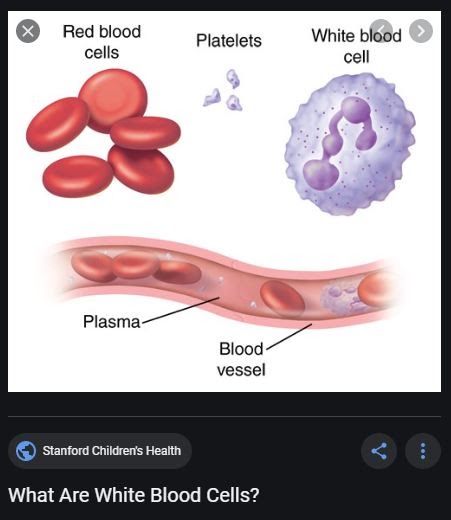

All three cell types form in the bone marrow, which is the soft tissue inside your bones.

Red blood cells transport oxygen to your body’s organs and tissues.

White blood cells help your body fight infections. Platelets help your blood to clot.